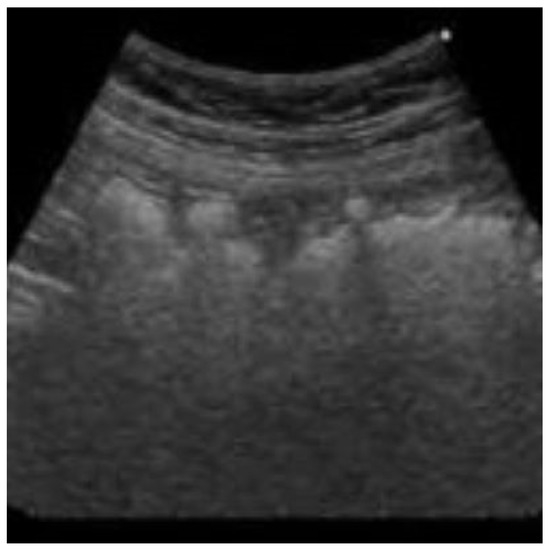

2. Case History

2.1. Differential Diagnosis, Investigations and Treatment